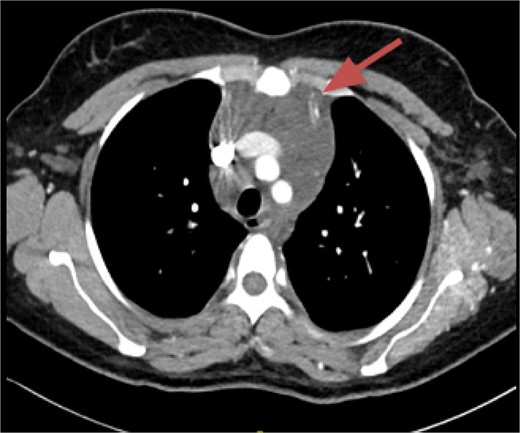

CT imaging, an anterior mediastinal mass was evident (Fig. 2), associated with the presence of thickening of interlobular septa in both lungs (Fig. 3). Surgery is carried out with diagnostic intent with suspicion of lymphoma vs DLP. A mass with cystic characteristics was found, thickening of interlobular septa and lymphatic channels that extended from the lung parenchyma to the mediastinum through the peribronchovascular space, dark serohematic pleural effusion without pleural lesions (Fig. 4).

The tomographic findings of DLP are interlobular septal thickening (70%), peribronchovascular interstitial thickening, ground glass opacities (80%), pleural effusion (40%), diffuse mediastinal infiltration (90%), and pleural thickening [2, 4], but no mediastinal mass is documented on CT. The radiological differential diagnoses of this disease are pulmonary edema, pulmonary veno-occlusive disease, pulmonary lymphangitic carcinomatosis, sarcoidosis, amyloidosis, primary pulmonary lymphoma, Erdheim-Chester disease, but these are not associated with mediastinal abnormalities [2].